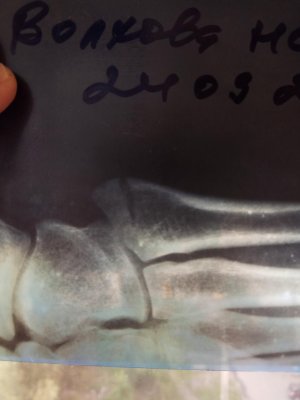

Перелом основания 5 плюсневой

24.09 сломала ногу. Сегодня 4.10 сказали динамики положительной нет, один врач говорит гипс на 4 недеди, другой твердит как минимум 6 плюс 2-4 недели реабилитация. По работе очень много приходиться ходить, понимаю, что вернусь не скоро, но не знаю какого врача слушать и хочу знать действительно ли нет вообще никакой динамики. Прикрепляю снимки: 24.09, 26.09 и 4.10 IMG_20171004_172546.jpg IMG_20171004_172630.jpg IMG_20171004_172701.jpg

24.09 сломала ногу. Сегодня 4.10 сказали динамики положительной нет, один врач говорит гипс на 4 недеди, другой твердит как минимум 6 плюс 2-4 недели реабилитация. По работе очень много приходиться ходить, понимаю, что вернусь не скоро, но не знаю какого врача слушать и хочу знать действительно ли нет вообще никакой динамики. Прикрепляю снимки: 24.09, 26.09 и 4.10Посмотреть вложение 14410 Посмотреть вложение 14411 Посмотреть вложение 14412

Здравствуйте! В ситуации с переломом ноги важно получить точную информацию о состоянии костей и динамике заживления. Обычно, если рентген показывает отсутствие положительной динамики, это может означать, что заживление идет медленнее, чем ожидалось. Время полного восстановления зависит от сложности перелома, возраста и общего состояния организма. Лучше всего обратиться к травматологу или ортопеду, который наблюдает за вашим лечением, чтобы получить конкретные рекомендации и понять реальную ситуацию.